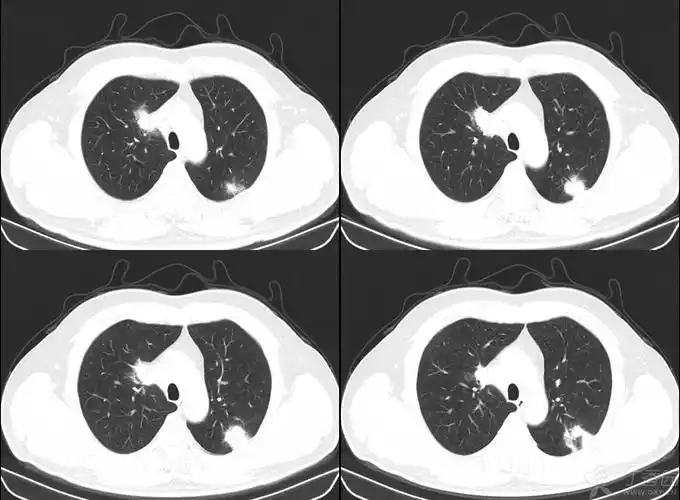

【讨论】双肺多发结节灶85149

影像读片双肺多发结节病例帖

多发肺结节,随访六年半,无变化